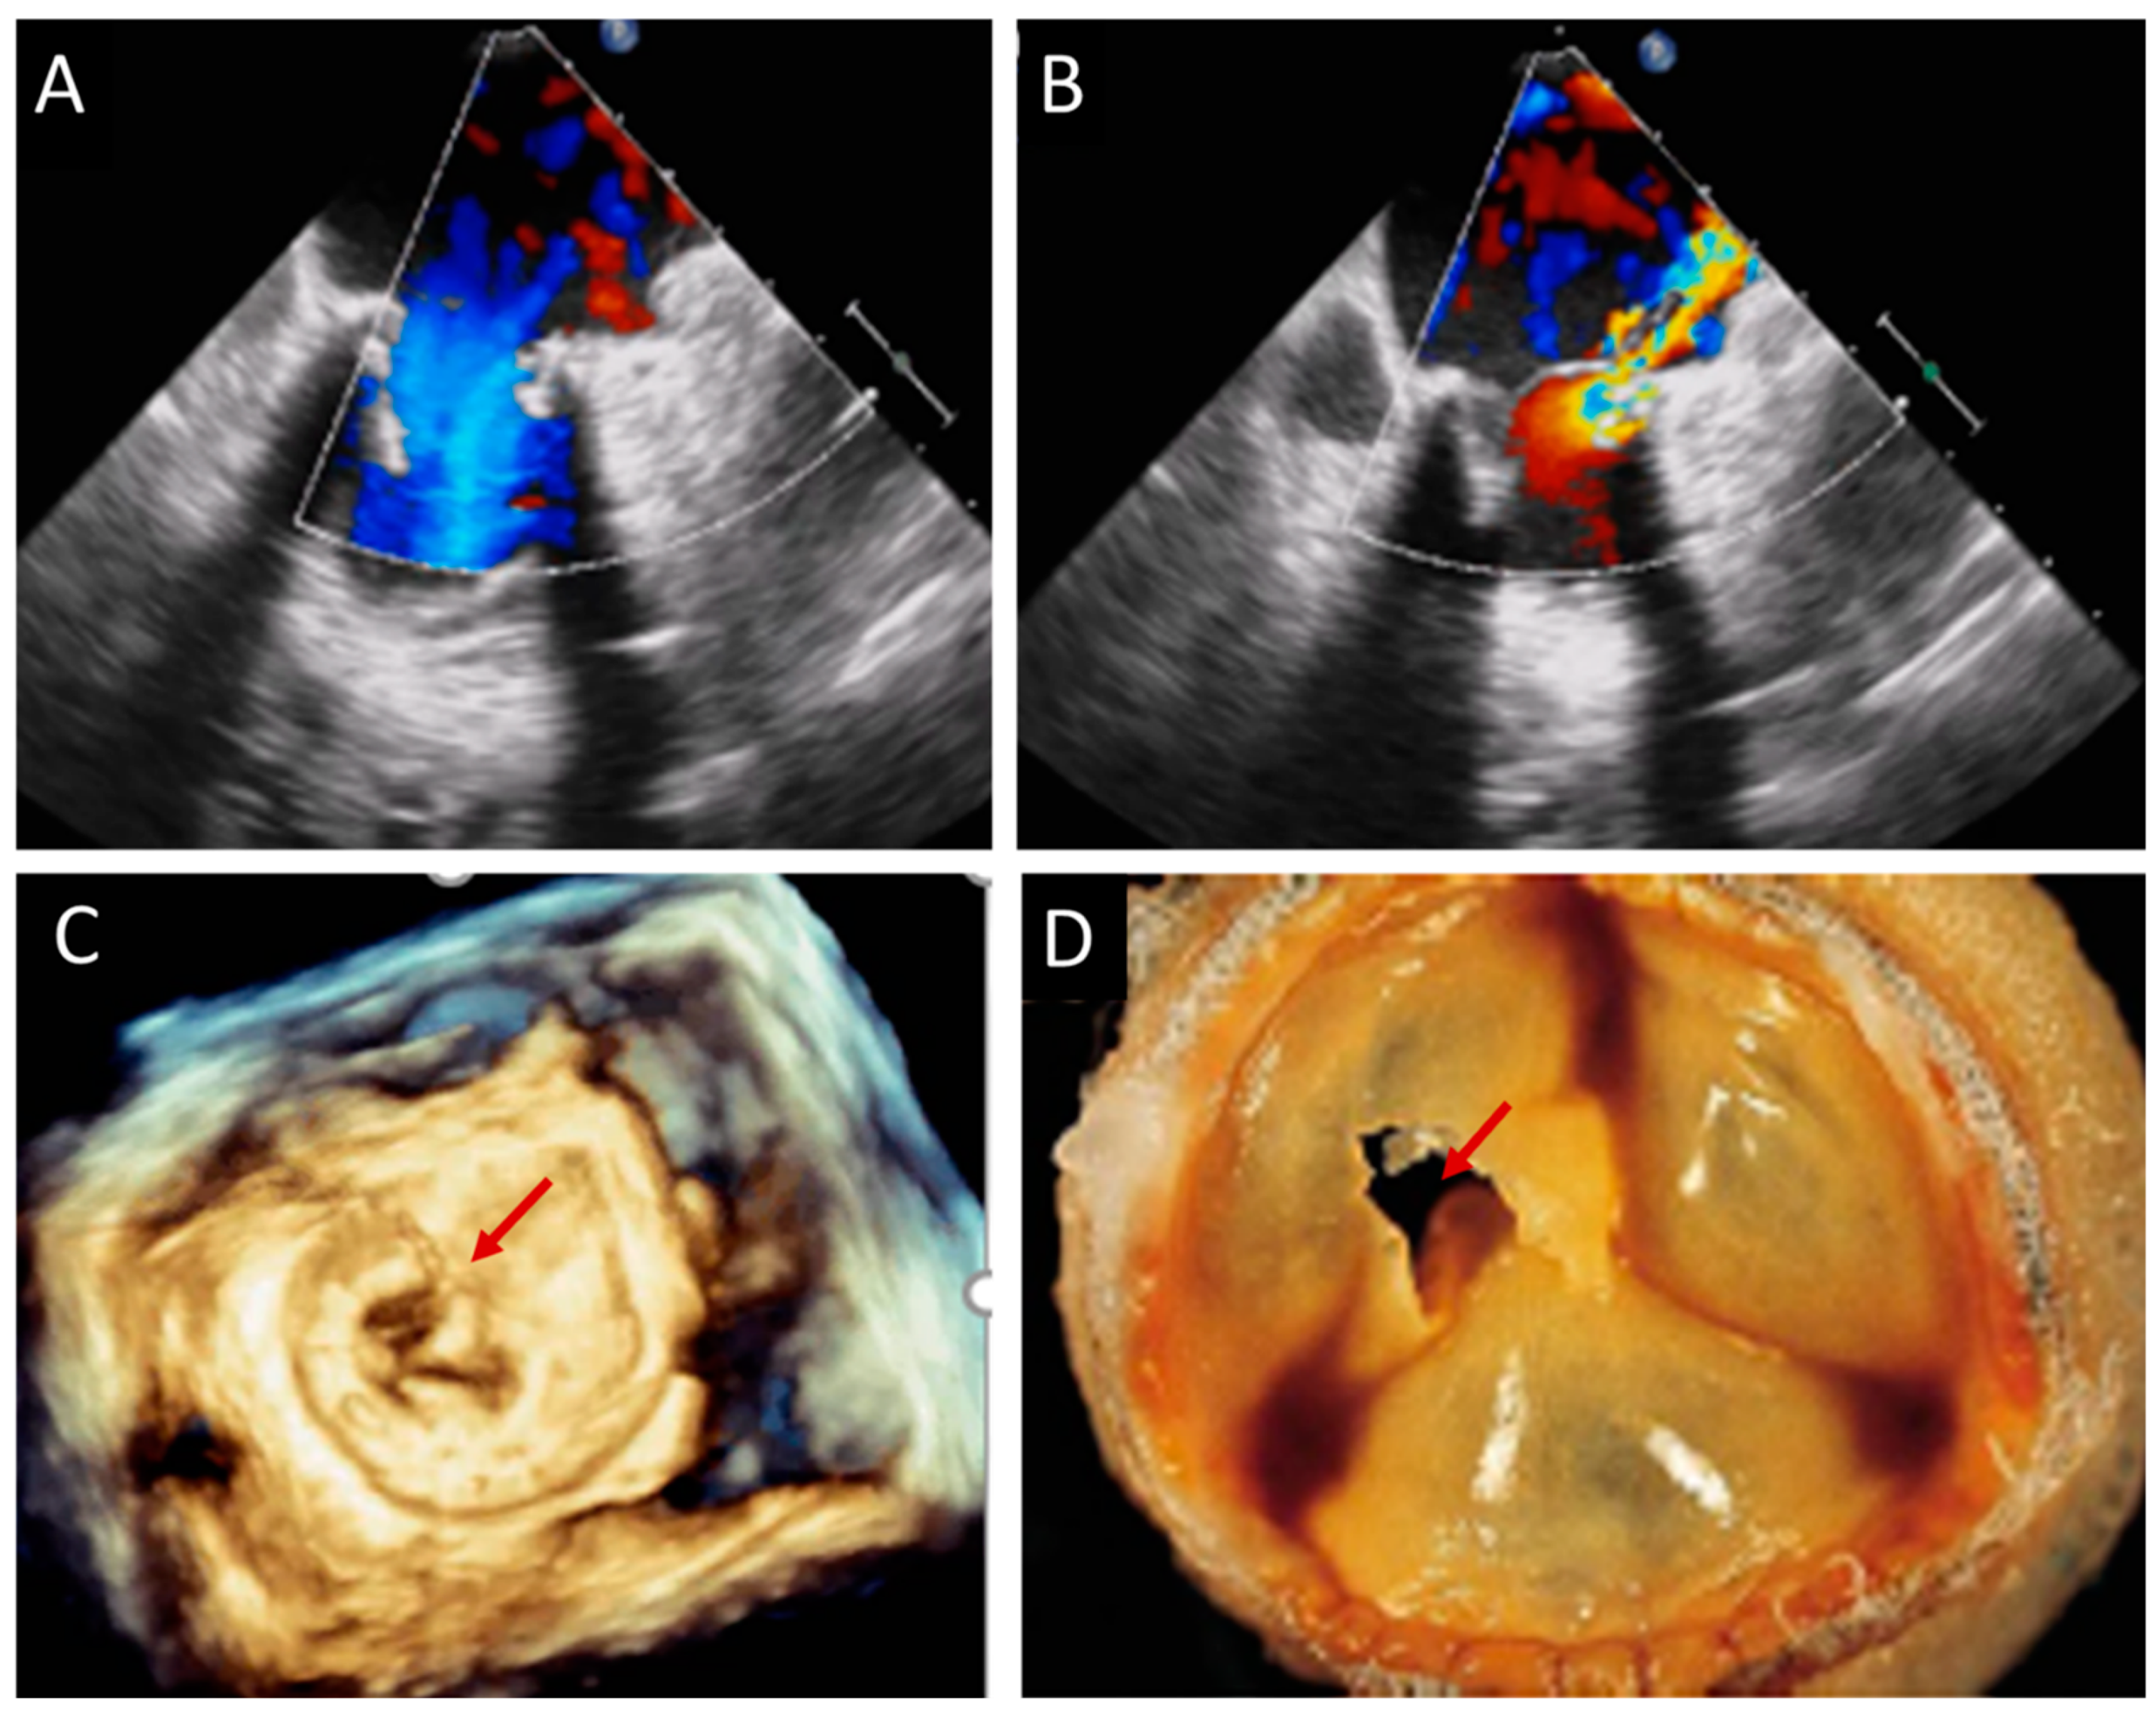

| TTE, TEE | Leaflet and/or ring thickening with diffuse or focal hyperechogenicity (calcifications). Reduced leaflet mobility. Leaflets’ fenestration, avulsion, or perforation. Stenosis or regurgitation. | Iso-hypoechogenic mass adherent to leaflets and ring, with leaflet thickening. Normal or reduced cusp mobility. More often, stenosis; regurgitation is uncommon. | Vegetations, diffuse or focal leaflets thickening, cusps perforation, wear or tear or cusp avulsion. Vegetation motion independent to cusps motion. Paravalvular complications: abscess, pseudo-aneurysm, fistula or dehiscence (and in some cases valve rocking) |

| CCT | Pannus (hypodense): HU ≥ 145; semicircular or circular structure located along leaflets’ surface or stent. Hyperdense leaflet thickening with or without calcifications, along with or without reduced mobility. | No calcifications. HU < 145. Hypoattenuated leaflet thickening (HALT), affecting (HAM) or reducing (RLM) leaflet motion. In some cases, large hypoattenuated mass. | Hypoattenuated mass adherent to leaflets or stent. Paravalvular complications: abscess, pseudo-aneurysm, fistula, or dehiscence. |